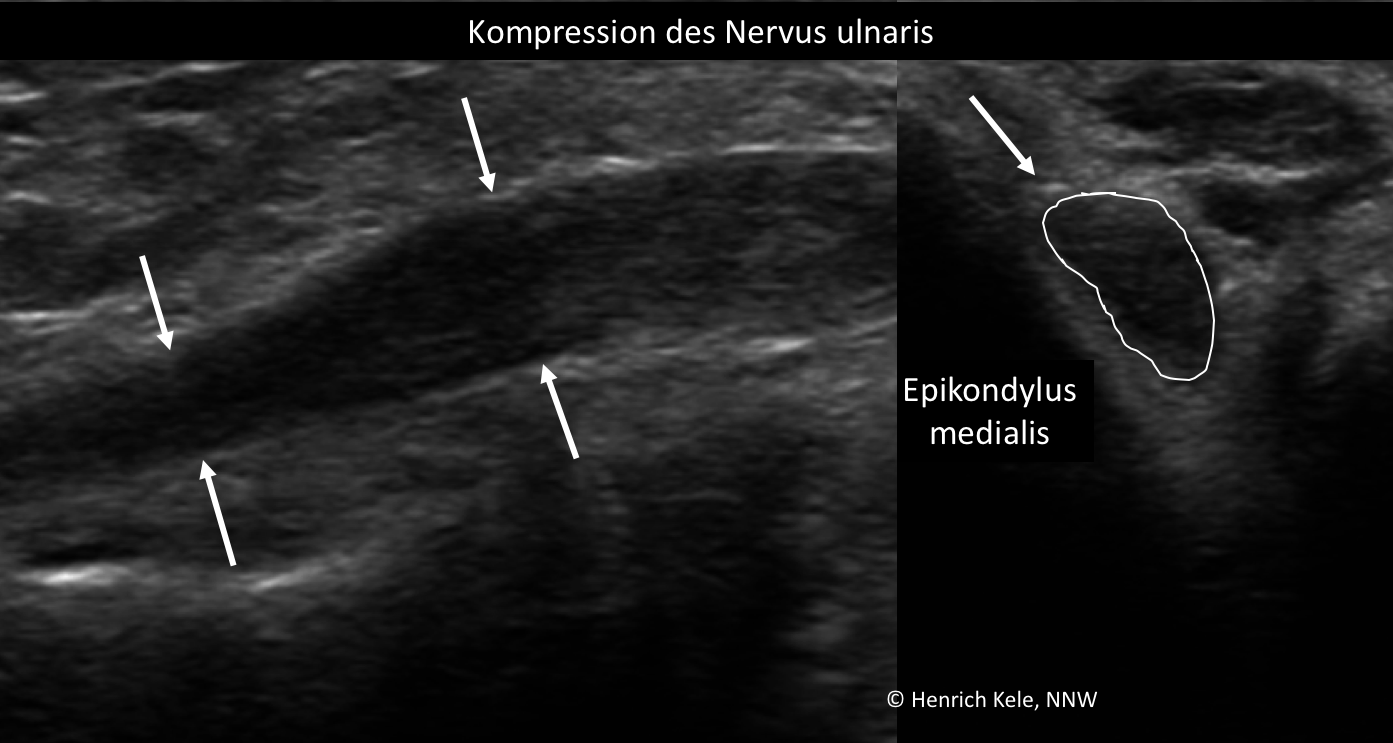

Die Diagnose wird durch EMG, ENG (NLG) und Nervensonografie gestellt. Letztere ist wichtig, insbesondere zur Abgrenzung einer Ulnaris-Druckschädigung und einer Ulnarisneuropathie am Ellenbogen von einer Kompression z.B. durch eine Arthrose oder Bandstrukturen.